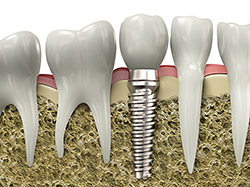

Implants

If you have missing teeth, it is crucial to replace them. Without all your teeth, chewing and eating can destabilize your bite and cause you discomfort. When teeth are missing, your mouth can shift and even cause your face to look older. Implants are a great way to replace your missing teeth, and if properly maintained, can last a lifetime!

An implant is a new tooth made of metal and porcelain that looks just like your natural tooth. It’s composed of two main parts: One part is the titanium implant body that takes the place of the missing root, and the second part is the tooth-colored crown that is cemented on top of the implant. With periodontal treatment, you can smile confidently knowing no one will ever suspect you have a replacement tooth.

In addition to tooth replacement, implants may be used to anchor dentures, especially lower dentures that tend to shift when you talk or chew. For patients with removable partial dentures, implants can replace missing teeth so you have a more natural-looking smile.